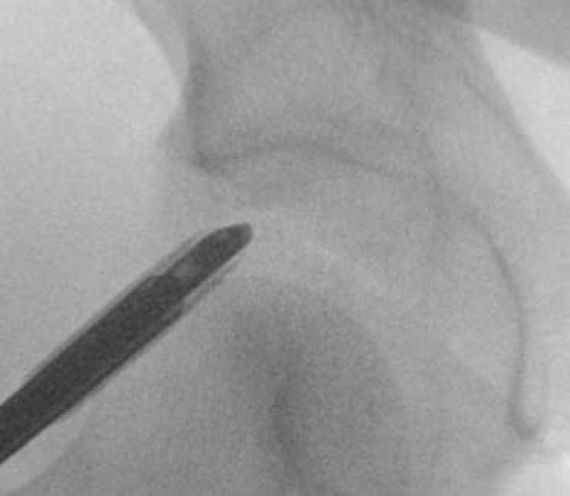

Hip conditions often improve with conservative treatment including a short course of rest, anti-inflammatory pain medication, and physical therapy. An ultrasound-guided cortisone injection is sometimes necessary for patients with persistent pain. If pain continues despite conservative treatment, hip arthroscopy is an excellent treatment option for patients with labral tears, femoroacetabular impingement (FAI), tears of the gluteus medius or proximal hamstring, among other conditions.